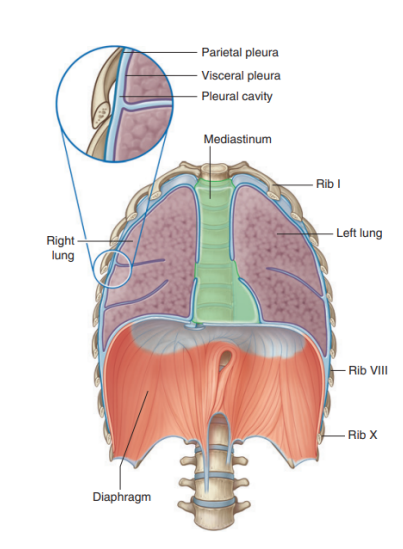

Lines of pleural reflection

Lines of pleural reflection —

Outline where parietal pleura abruptly change direction

As it passes from one wall of the pleural cavity to another

Superiorly —

Pleural cavity can project above the first costal cartilage but not above the neck of rib I

Due to inferior slope of rib I to its articulation with the manubrium

Anteriorly —

Pleural cavities approach each other posteriorly to the upper part of the sternum

Parietal pleura (posterior to lower sternum) doesn’t come to midline on the left the same way it does on the right

Due to presence of the middle mediastinum and its structures causing a bulging to the left

Inferiorly —

Costal pleura reflects onto the diaphragm above the costal margin

Also some vertical lines indicating extension of pleural cavity

Vertical lines indicating extension of the pleural cavity

Midclavicular line —

Pleural cavity extends inferiorly from the clavicles to approximately rib VIII

Midaxillary line —

Extends to rib X

Inferior margin of the parietal pleura takes an oblique path laterally from the level of rib VII in the midclavicular line to rib X in the midaxillary line and the T12 vertebra at the vertebral columns

Surface anatomy relating to the fissures and lobes

Palpable surface landmarks —

Can be used to visualize the normal outlines of the pleural cavities & lungs & to determine the positions of the pulmonary lobes & fissures —ex.

Superiorly, we can see the parietal pleura projects above the first costal cartilage & anteriorly approaches the midline posterior to the sternum (uppermost section). Left parietal pleura doesn’t come close to the midline as much as the right lobe due to the heart bulging on the left side

Inferiorly, the pleura reflects on the diaphragm, above the costal margin & courses around the thoracic wall following an VIII, X, XII contour

(Ie. rib VIII in the midclavicular line, rib X in the midaxillary line, and vertebra TXII posteriorly)

Lungs don’t completely fill areas surrounded by pleural cavities — particularly anteriorly & inferiorly —

Costomediastinal recesses —

Occur anteriorly, particularly on the left side in relationship to the heart bulge

Costodiaphragmatic recesses —

Occur inferiorly between the lower lung margin & the lower margin of the pleural cavity

Margins of lungs related to ribs

Inferior lung margin —

Found at bottom of the thoracic wall, following a VI, VIII, X contour (ie. rib VI in the midclavicular line, rib VIII in the midaxillary line, and vertebra TX posteriorly)